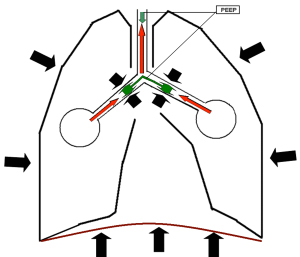

Recruitment (mobilizáció alvás alveolusok).

Az ARDS (akut légzőszervi szindróma distresc, ARDS - akut légzési distressz szindróma) az alveolusok van a „gubancos” állapotban, és nem vesz részt a gázcserét. Az ilyen tapadás megsértése miatt a tulajdonságok a tüdő felületaktív anyag és kóros váladékok a lumen a léghólyagok. Felvétel - ez egy eszközkezelő manőverezni a lélegeztetőgép, amelyben miatt a megfelelő kiválasztása belégzési nyomás, a belégzési időtartamát és a növekvő PEEP elérni Straightening összeragadt alveolusok. Befejeződése után Recruitment manever (mobilizáció manőver alveolusok) fenntartásához a léghólyagok az expandált állapotban, a lélegeztető folytatja PEEP.

PEEP - egy lehetőség, hogy be van ágyazva a különböző közlekedési módok szellőztetés.

CPAP állandó pozitív légúti nyomás (folyamatos pozitív légúti nyomás). Ezt a lehetőséget meg kell érteni, mint egy állandó fizikai vagy matematikai kifejezést :. „Mindig ugyanaz” Intelligens ventilátor PPV ha ez az opció engedélyezve van, virtuóz „játszik” és kilégzést szelepek, akkor az állandó nyomás fenntartása ugyanazon légzőkörben. CPAP beállítás vezérlő logika szerint működik jeleket a nyomásérzékelő. Amikor a beteg belélegez, a belégzés szelep nyit enyhén fenntartása érdekében szükség szerint a nyomás egy adott szinten. Kilégzéskor, összhangban a vezérlő utasítás a kipufogószelep kissé nyílik, hogy a fölös levegő légzőkörben.

Abban az esetben, ha az opció kiegészítve CPAP semmilyen szellőztetési mód, helyesebb nevezni Baseline nyomás, mert abban az időben a hardver belégzési nyomás (nyomás) nem állandó.

Kiindulási nyomást vagy csak alapvonal a vezérlőpulton a ventilátor általában hagyományosan jelöljük PEEP / CPAP az előre meghatározott nyomás szintje a légzőkörben, amely eszközt is megmarad az a közötti intervallum légzési ciklusok. Kiindulási fogalma nyomás, a modern koncepciók, a leginkább megfelelő azonosítja ezt az opciót szellőztető, de fontos tudni, hogy a gazdálkodás elvét PEEP, CPAP és Baseline ugyanaz. Nyomás a gráf - ez az egyik, és ugyanabban a szegmensben a «Y» tengelyen, és valójában, mondhatjuk a PEEP, CPAP és alapvonal szinonimaként. Abban az esetben, PEEP = 0, ez ZEEP (nulla kilégzési nyomás), és az alapszintű megfelel a légköri nyomás.